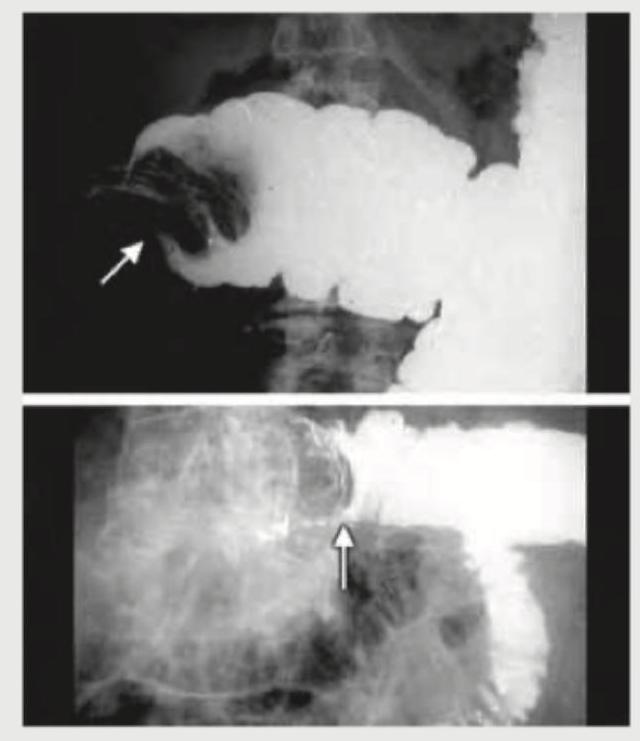

A baby presents with colicky abdominal pain. Mother gives a history of bloody stools. All the statements regarding this condition are true except:

Explanation: ***Rate of re-occurrence is $50 \%$ after non-operative reduction*** - The recurrence rate of intussusception after successful non-operative reduction (e.g., pneumatic or hydrostatic enema) is typically quoted as **5-15%**, not 50%. - A 50% recurrence rate would be unusually high and is not supported by standard clinical data. *Diagnosis is confirmed by USG* - **Ultrasound (USG)** is the preferred initial imaging modality for suspected intussusception due to its high sensitivity and specificity. - The classic "**target sign**" or "**donut sign**" on ultrasound confirms the diagnosis. *Seventy percent of the cases can be reduced nonoperatively* - **Non-operative reduction** using pneumatic or hydrostatic enema is successful in approximately **70-75%** of cases of intussusception, especially when performed early. - This method is often the first-line treatment if there are no signs of peritonitis or perforation. *Baby may present with red currant jelly stools* - **Red currant jelly stools** (stools mixed with blood and mucus) are a classic clinical manifestation of intussusception. - This symptom results from the vascular compromise and mucosal ischemia in the telescoping bowel segment.

Explanation: ***Treatment of choice in this condition is resection and anastomosis*** - The initial treatment for **intussusception** in stable patients without signs of peritonitis or perforation is typically **non-operative reduction** using a pneumatic or hydrostatic enema. - **Surgical resection and anastomosis** are reserved for cases that fail enema reduction, have evidence of perforation, peritonitis, or bowel necrosis, or in cases where a pathological lead point is identified later. *Most common age of presentation is between 6-9 months* - This statement is true. The peak incidence of **intussusception** occurs between **5 and 9 months of age**, with 80-90% of cases presenting by 2 years of age. - This age range coincides with changes in diet and development of the intestinal immune system, which can contribute to the hypertrophy of lymphoid tissue. *Most common site is ileocolic* - This statement is true. **Ileocolic intussusception**, where the ileum telescopes into the colon through the ileocecal valve, accounts for about **75-90% of all cases**. - This anatomical arrangement at the ileocecal junction is particularly prone to telescoping. *Most common cause of this condition is hypertrophy of Peyer's patches* - This statement is true, particularly in infants and young children where a specific lead point is not found. - **Hypertrophy of Peyer's patches** during viral illnesses (e.g., adenovirus) or other infections is thought to act as a *lead point*, initiating the invagination process.

Explanation: ***Rate of reoccurrence is 50% after nonoperative reduction*** - The recurrence rate after successful nonoperative reduction of intussusception is typically around **5-10%**, not as high as 50%. - A 50% recurrence rate would suggest a highly unstable reduction or a strong underlying predisposing factor that is not being addressed. *Ileo-colic variety is common in children* - **Ileo-colic intussusception** is indeed the most common type of intussusception, especially in children, accounting for approximately 90% of cases. - This anatomical location is where the **ileum telescopes into the cecum and colon**, which is often depicted in images like the one provided. *70% of the cases can be reduced nonoperatively* - **Nonoperative reduction** using air or hydrostatic enema is successful in a significant majority of intussusception cases, with success rates often reported between **70-90%**. - This makes nonoperative reduction the first-line treatment in stable patients without signs of peritonitis or perforation. *Baby presents with red currant jelly stools* - **Red currant jelly stools**, which are a mixture of **blood and mucus**, are a classic symptom of intussusception, particularly in infants. - This symptom results from **ischemia and sloughing of the intestinal mucosa** due to compromised blood supply.

Explanation: ***Acute intussusception*** - The classic triad of symptoms in an infant – **intermittent abdominal pain** (screaming, drawing up legs), **vomiting**, and **currant jelly stools** (blood-stained mucus) – is highly indicative of intussusception. - The presence of a **"dance sign"** (emptiness in the right iliac fossa due to the displacement of the cecum) and a palpable sausage-shaped mass (though not explicitly stated, implied by emptiness) further supports this diagnosis. *Rectal prolapse* - While rectal prolapse can present with crying and blood in the stool, it would typically involve the **visible protrusion of rectal tissue from the anus**, which is not described. - It does not cause the intermittent severe abdominal pain and listlessness consistent with an acute intestinal obstruction. *Midgut volvulus* - Midgut volvulus typically presents with **bilious vomiting** and signs of acute intestinal obstruction and ischemia (e.g., severe abdominal distension, peritonitis, shock). - While it can cause bloody stools due to ischemia, the characteristic **intermittent pain and asymptomatic periods** between attacks, along with the specific rectal findings, are more characteristic of intussusception. *Caecal volvulus* - Caecal volvulus is more common in **older children or adults** and presents with acute abdominal pain, distension, and signs of large bowel obstruction. - It would not typically present with the intermittent episodes of pain and the classic **"currant jelly" stools** or the "dance sign" seen in intussusception in an infant.